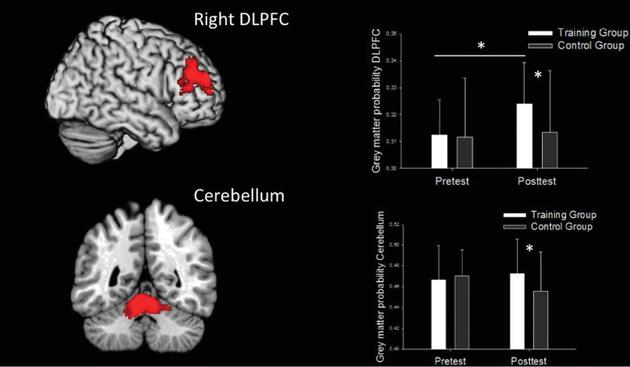

那DLPFC跟玩电子游戏又有什么关系呢?有德国科学家在14岁左右青少年中研究发现,跟不经常玩游戏的相比,常玩游戏的其DLPFC区的脑皮层更厚;不常玩游戏的青少年每天玩半个小时,持续两到三个月,这个脑区的体积是增大的。这些结果都可解释为玩游戏锻炼了DLPFC。这些被试既不“上瘾”,也不是职业玩家。

德国科学家研究发现:青少年在两个月内每天玩至少半个小时的《超级玛丽》,其右侧大脑的背外侧前额叶区(DLPFC)和小脑(cerebellum)中的灰质密度会增加,提示这些脑区在玩游戏的过程中得到了锻炼

德国科学家研究发现:青少年在两个月内每天玩至少半个小时的《超级玛丽》,其右侧大脑的背外侧前额叶区(DLPFC)和小脑(cerebellum)中的灰质密度会增加,提示这些脑区在玩游戏的过程中得到了锻炼有趣的是,我们自己最近的一项研究表明:在校大学生在玩《英雄联盟》这款游戏时,其DLPFC大多数时候却是处于一种抑制的状态。这似乎跟德国科学家的研究结果矛盾了。如何解释这个矛盾呢?我们猜想,这可能与游戏种类有关。在德国科学家的研究中,青少年玩的大多是《超级玛丽》这一类的单人冒险类游戏,而我们研究的《英雄联盟》是多人在线动作类游戏。玩家在不同种类游戏中所采用的策略、进行的游戏操作以及可能得到的奖赏都是不一样的。这可能就决定了DLPFC在游戏中是激活还是抑制,是得到了锻炼还是被“关机”了。比如,我们发现《英雄联盟》玩家在游戏中击杀对手后DLPFC会出现最为显著的抑制,这可能与玩家那一瞬间正处于一种“杀红眼”的状态有关。